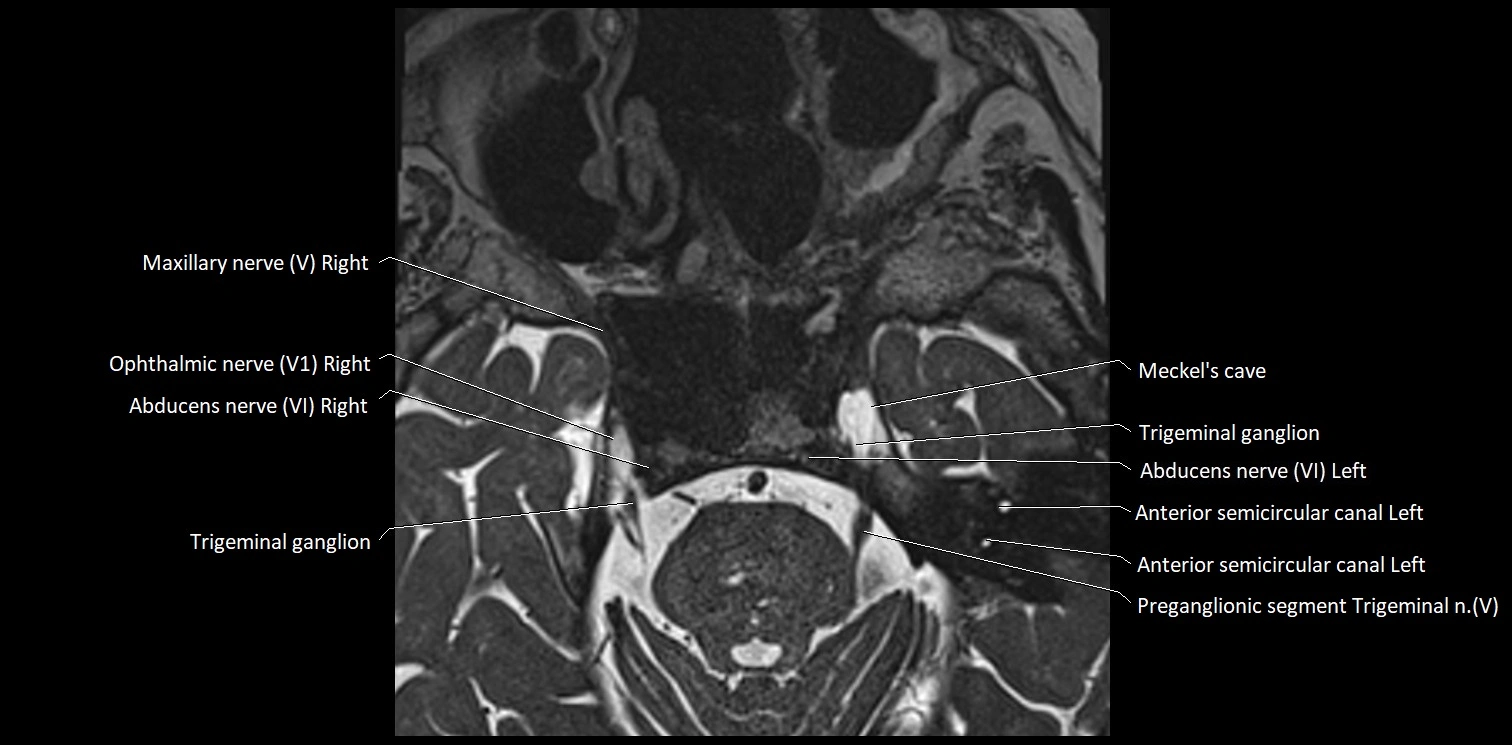

MRI Appearance

• The abducens nerve is a small, thin, linear structure

• Best visualized on high-resolution T2-weighted 3D MRI sequences (e.g., FIESTA or CISS)

• Seen as a hypointense (dark) line running from the brainstem at the pontomedullary junction, traversing the prepontine cistern, and entering Dorello’s canal under the petrosphenoidal ligament, then into the cavernous sinus, and finally the orbit

• May be challenging to visualize in standard MRI due to its small size

• Pathology may be inferred by absence, displacement, or enhancement of the nerve

MRI images

image